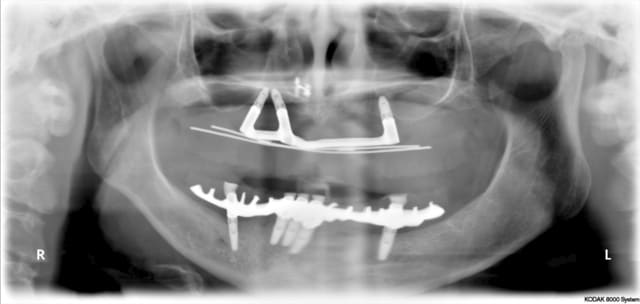

non mais il a quand même fallu que je l'a reçoive une fois pour lui dire que ce n'était pas de mon ressort. J'en ai profité pour lui faire cette magnifique pano